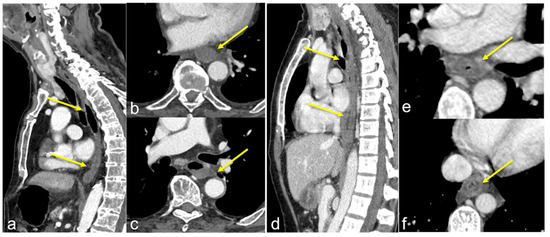

| Aorto-Enteric Fistula (Figure 31) | Bleeding in a patient with a history of surgery for aortic aneurysm. | A connection between the aorta and the intestinal lumen. Absence of adipose cleavage planes. |